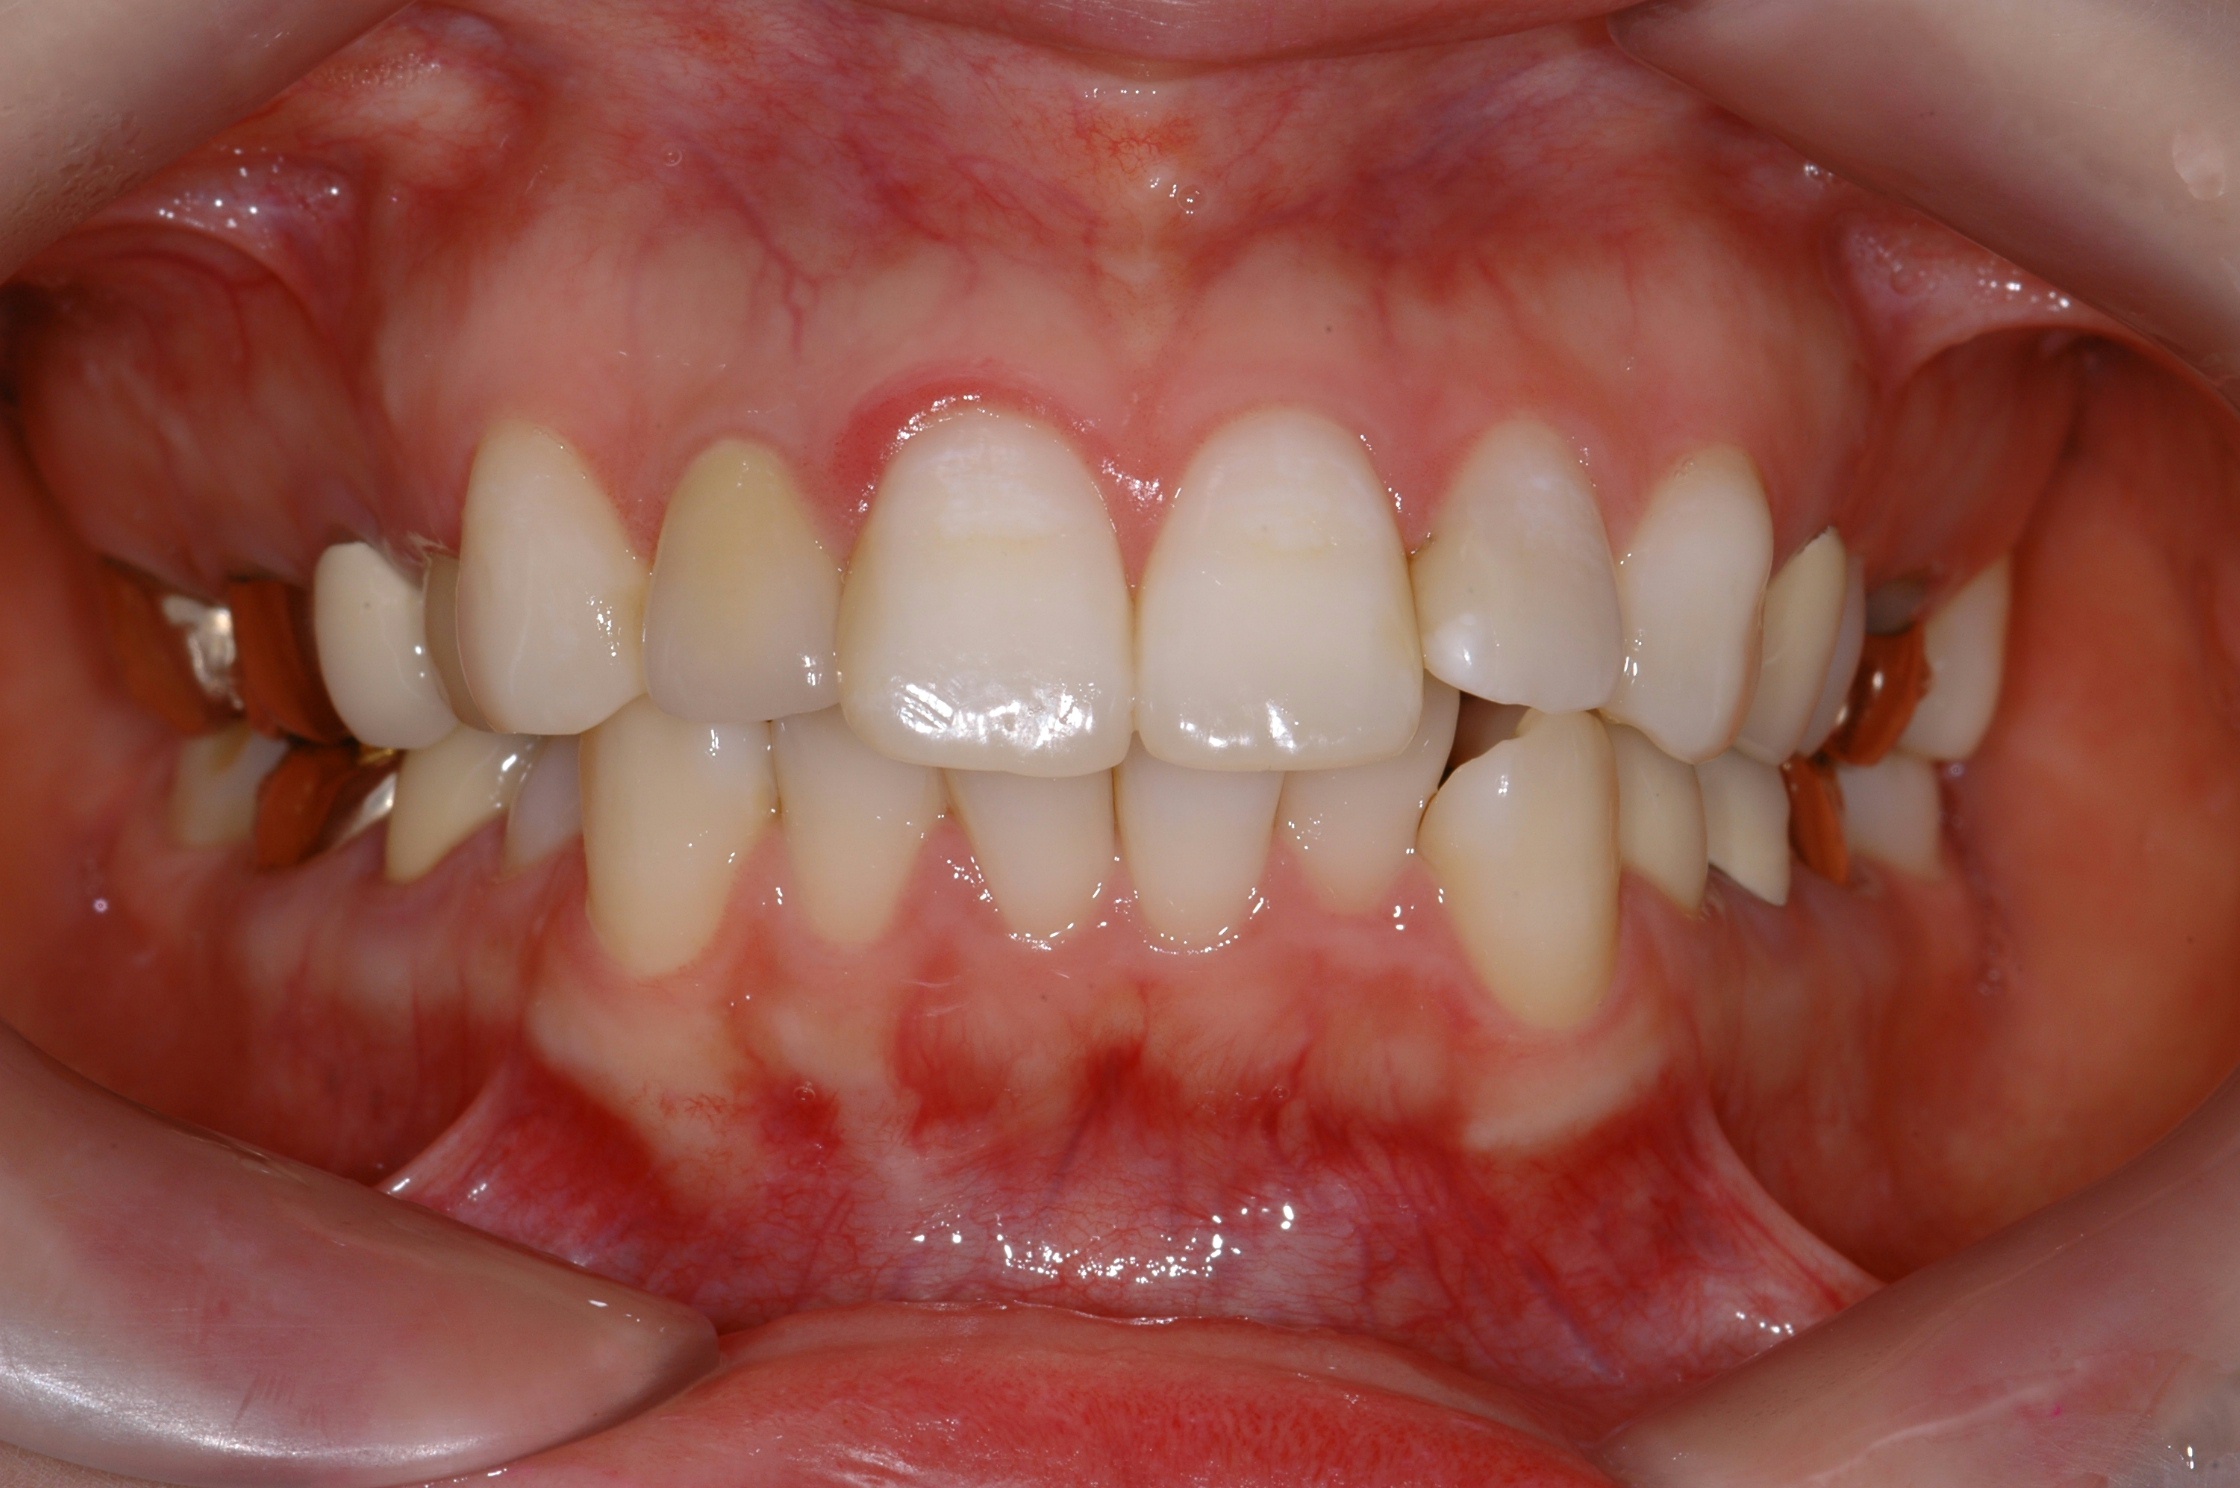

치료 후 사진입니다.